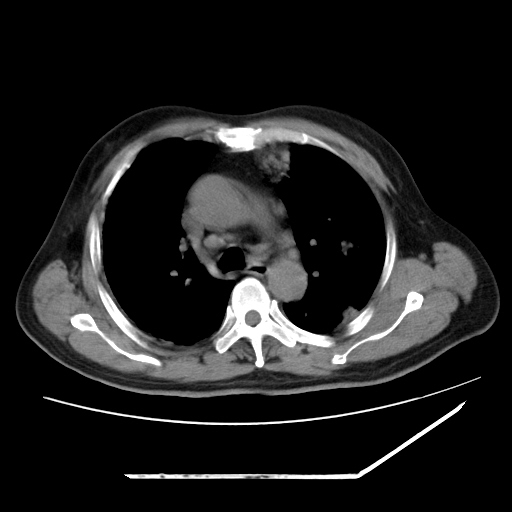

男,57,畏寒,发热

两肺野多发大小不一高密度灶,纵膈内见肿大淋巴结,要考虑转移瘤可能。双侧胸腔少量积液。

双肺多发结节样病灶,部分内见透光区,纵隔内见淋巴结肿大。结核临床如有畏寒,高热,白细胞增高首先考虑迁徙性肺脓肿(多是金黄色葡萄球菌感染)。

注意除外转移瘤。

1)考虑两肺感染性病变(金黄色葡萄球菌肺炎?);建议抗炎治疗后复查排除其他。2)双侧少量胸腔积液。